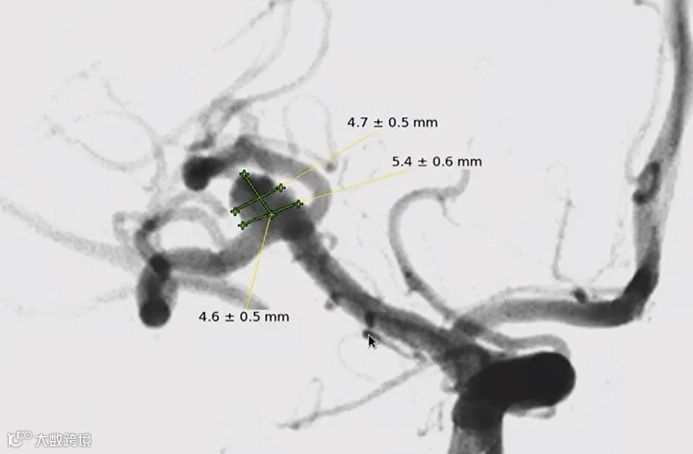

动脉瘤测量结果:动脉瘤平均宽度4.7mm,高度4.6mm,瘤颈宽度5.4mm。

经测量后充分评估,选用WEB™ SL6×3mm进行动脉瘤栓塞治疗